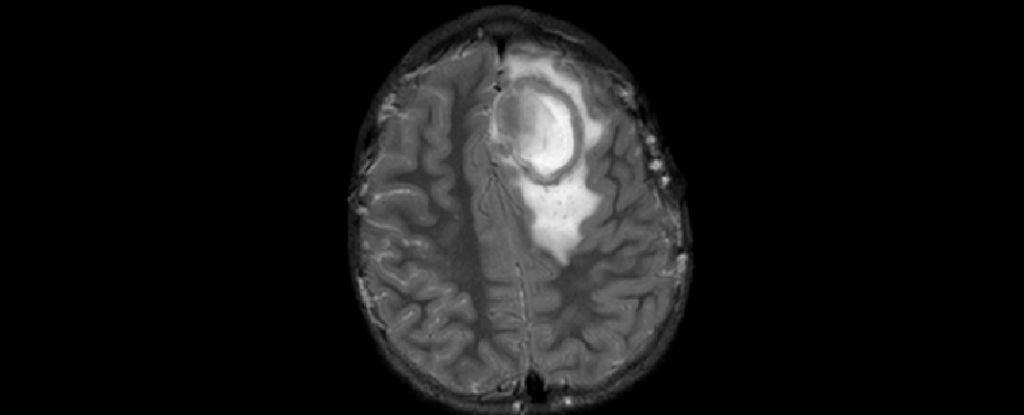

Silent Tooth Infection Reveals Life-Threatening Brain Abscess

A man in the UK was diagnosed with a life-threatening brain abscess caused by an infected cracked tooth, despite having no oral symptoms. He underwent emergency brain surgery and treatment for sepsis, and is now recovering with ongoing therapy. The case highlights the importance of prompt medical attention for infections that can lead to severe complications.